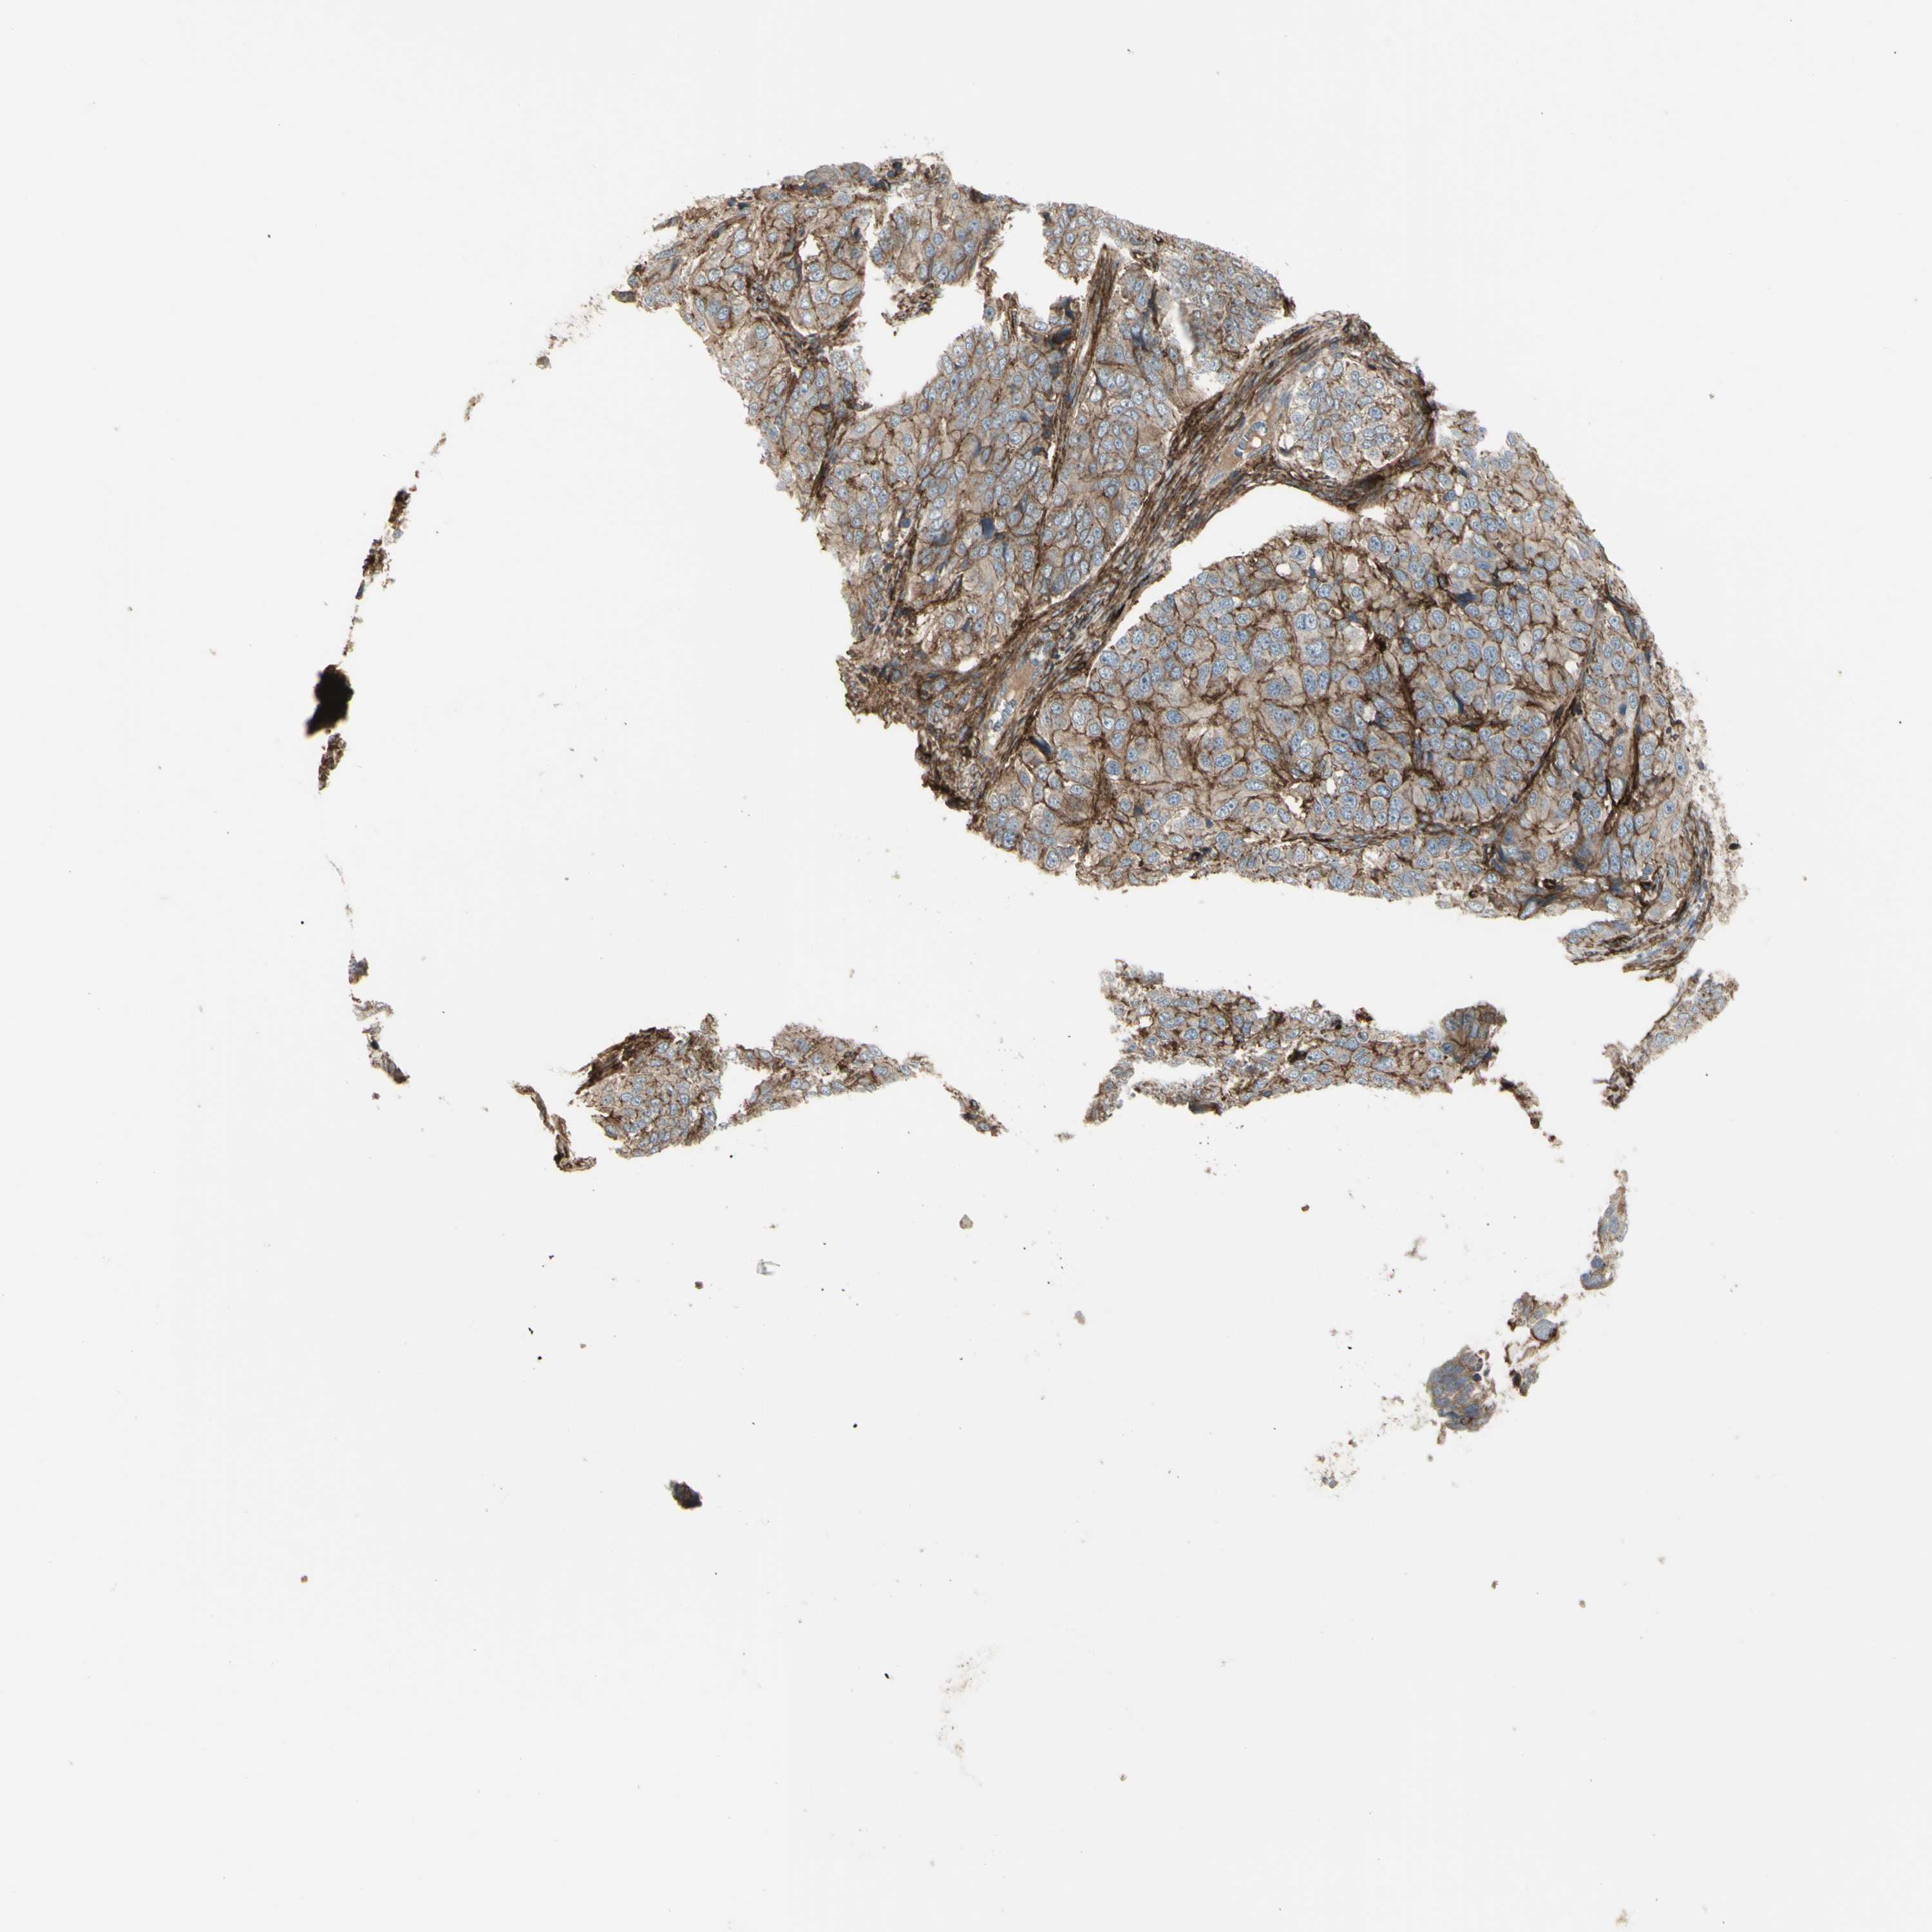

OVARIAN CANCER - Protein expressioni

A mouse-over function shows sample information and annotation data. Click on an image to view it in a full screen mode. Samples can be filtered based on level of antibody staining by selecting one or several of the following categories: high, medium, low and not detected. The assay and annotation is described here.

Note that samples used for immunohistochemistry by the Human Protein Atlas do not correspond to samples in the TCGA dataset.

Antibody stainingi

Antibody staining in the annotated cell types in the current human tissue is reported as not detected, low, medium, or high, based on conventional immunohistochemistry profiling in selected tissues. This score is based on the combination of the staining intensity and fraction of stained cells.

Each image is clickable and will lead to virtual microscopy that enables deeper exploration of all samples and also displays staining intensity scores, fraction scores and subcellular localization as well as patient and tissue information for each sample.

Antibody HPA009285

Antibody HPA017139

Antibody CAB017826

Cystadenocarcinoma, serous, NOS

Carcinoma, endometroid

Cystadenocarcinoma, mucinous, NOS

Carcinoma, NOS